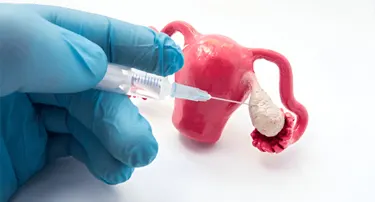

Uterine Prolapse Treatment Without Hysterectomy – Robotic Options

Uterine prolapse happens when the muscles and ligaments in the pelvic area become weak, causing the uterus to sag into the vaginal canal.

Robotic Oophorectomy: Indications, Recovery & Hormonal Effects

Oophorectomy refers to major surgery in which one or both of the ovaries are removed. It is recommended for treating various gynecological conditions, such as ovarian cysts, tumors, or endometriosis.

Robotic Ovarian Cyst Removal: Cost, Recovery & Risks

Ovarian cysts are a commonly occurring condition among women. Mostly, ovarian cysts are small and do not cause any health issues.

Robotic Myomectomy for Fibroids: Fertility, Recovery & Success Rates

If you or the ones you care for are diagnosed with fibroids, your doctor may advise myomectomy, which involves the surgical removal of fibroids.